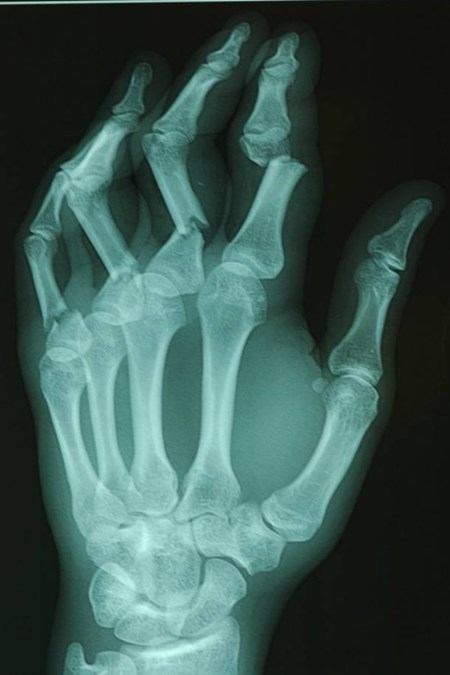

= fracturen van middenhandsbeentjes en vingerfracturen

In metacarpaal fracturen en in vingerfracturen wordt gestreefd naar onmiddellijke mobilisatie, om verstijving van de hand te voorkomen.